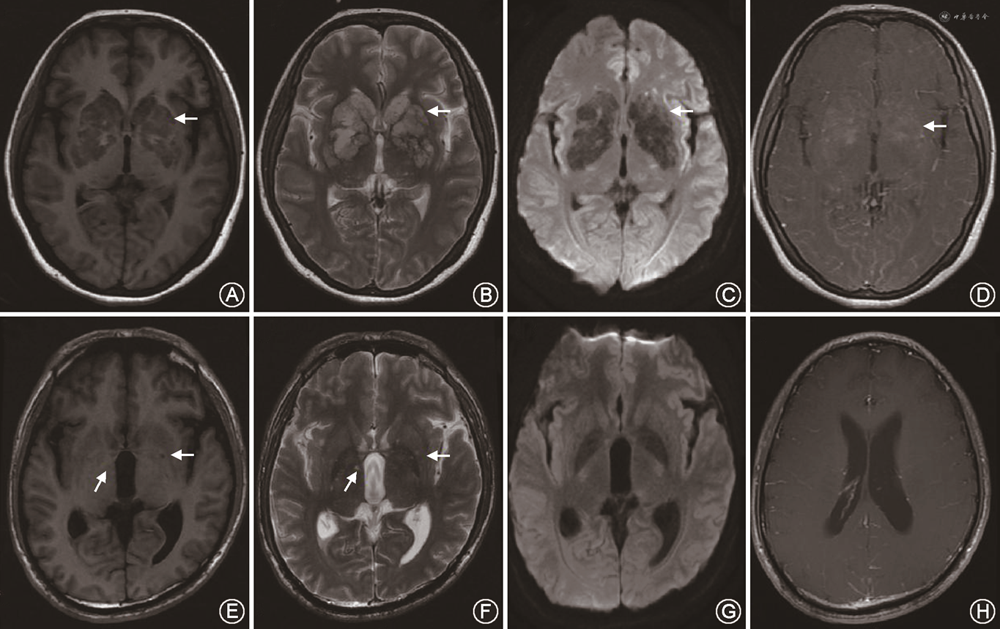

隐球菌性脑膜炎的影像学表现包括:软脑膜和硬脑膜强化、扩张的血管周围间隙、胶状假性囊肿、隐球菌瘤、肉芽肿、脑积水、脑萎缩、血管炎等,但仅有21%~27%的病例在MRI上有典型的隐球菌性脑膜炎影像学表现(图2)[29]。影像学表现受患者免疫状态和治疗反应的影响,免疫功能低下者,炎性反应较轻或不存在,影像学可无特殊表现,当通过抗真菌和HAART治疗,患者免疫力得到恢复,机体出现炎性反应以限制感染,形成脓肿或肉芽肿。因此,胶状假性囊肿、隐球菌瘤或脑膜强化等在免疫功能低下者中相对少见,而更多见于免疫功能正常的患者[30]。